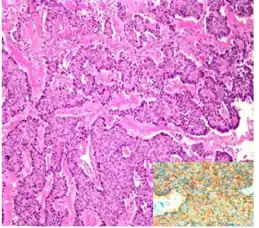

| Micrograph of a strumal carcinoid. H&E stain. | |

The strumal carcinoid is a type of monodermal teratoma with histomorphologic features of (1) the thyroid gland and (2) a neuroendocrine tumour (carcinoid).[1][2]

Strumal carcinoid, strongly positive for synaptophysin stain (inset)